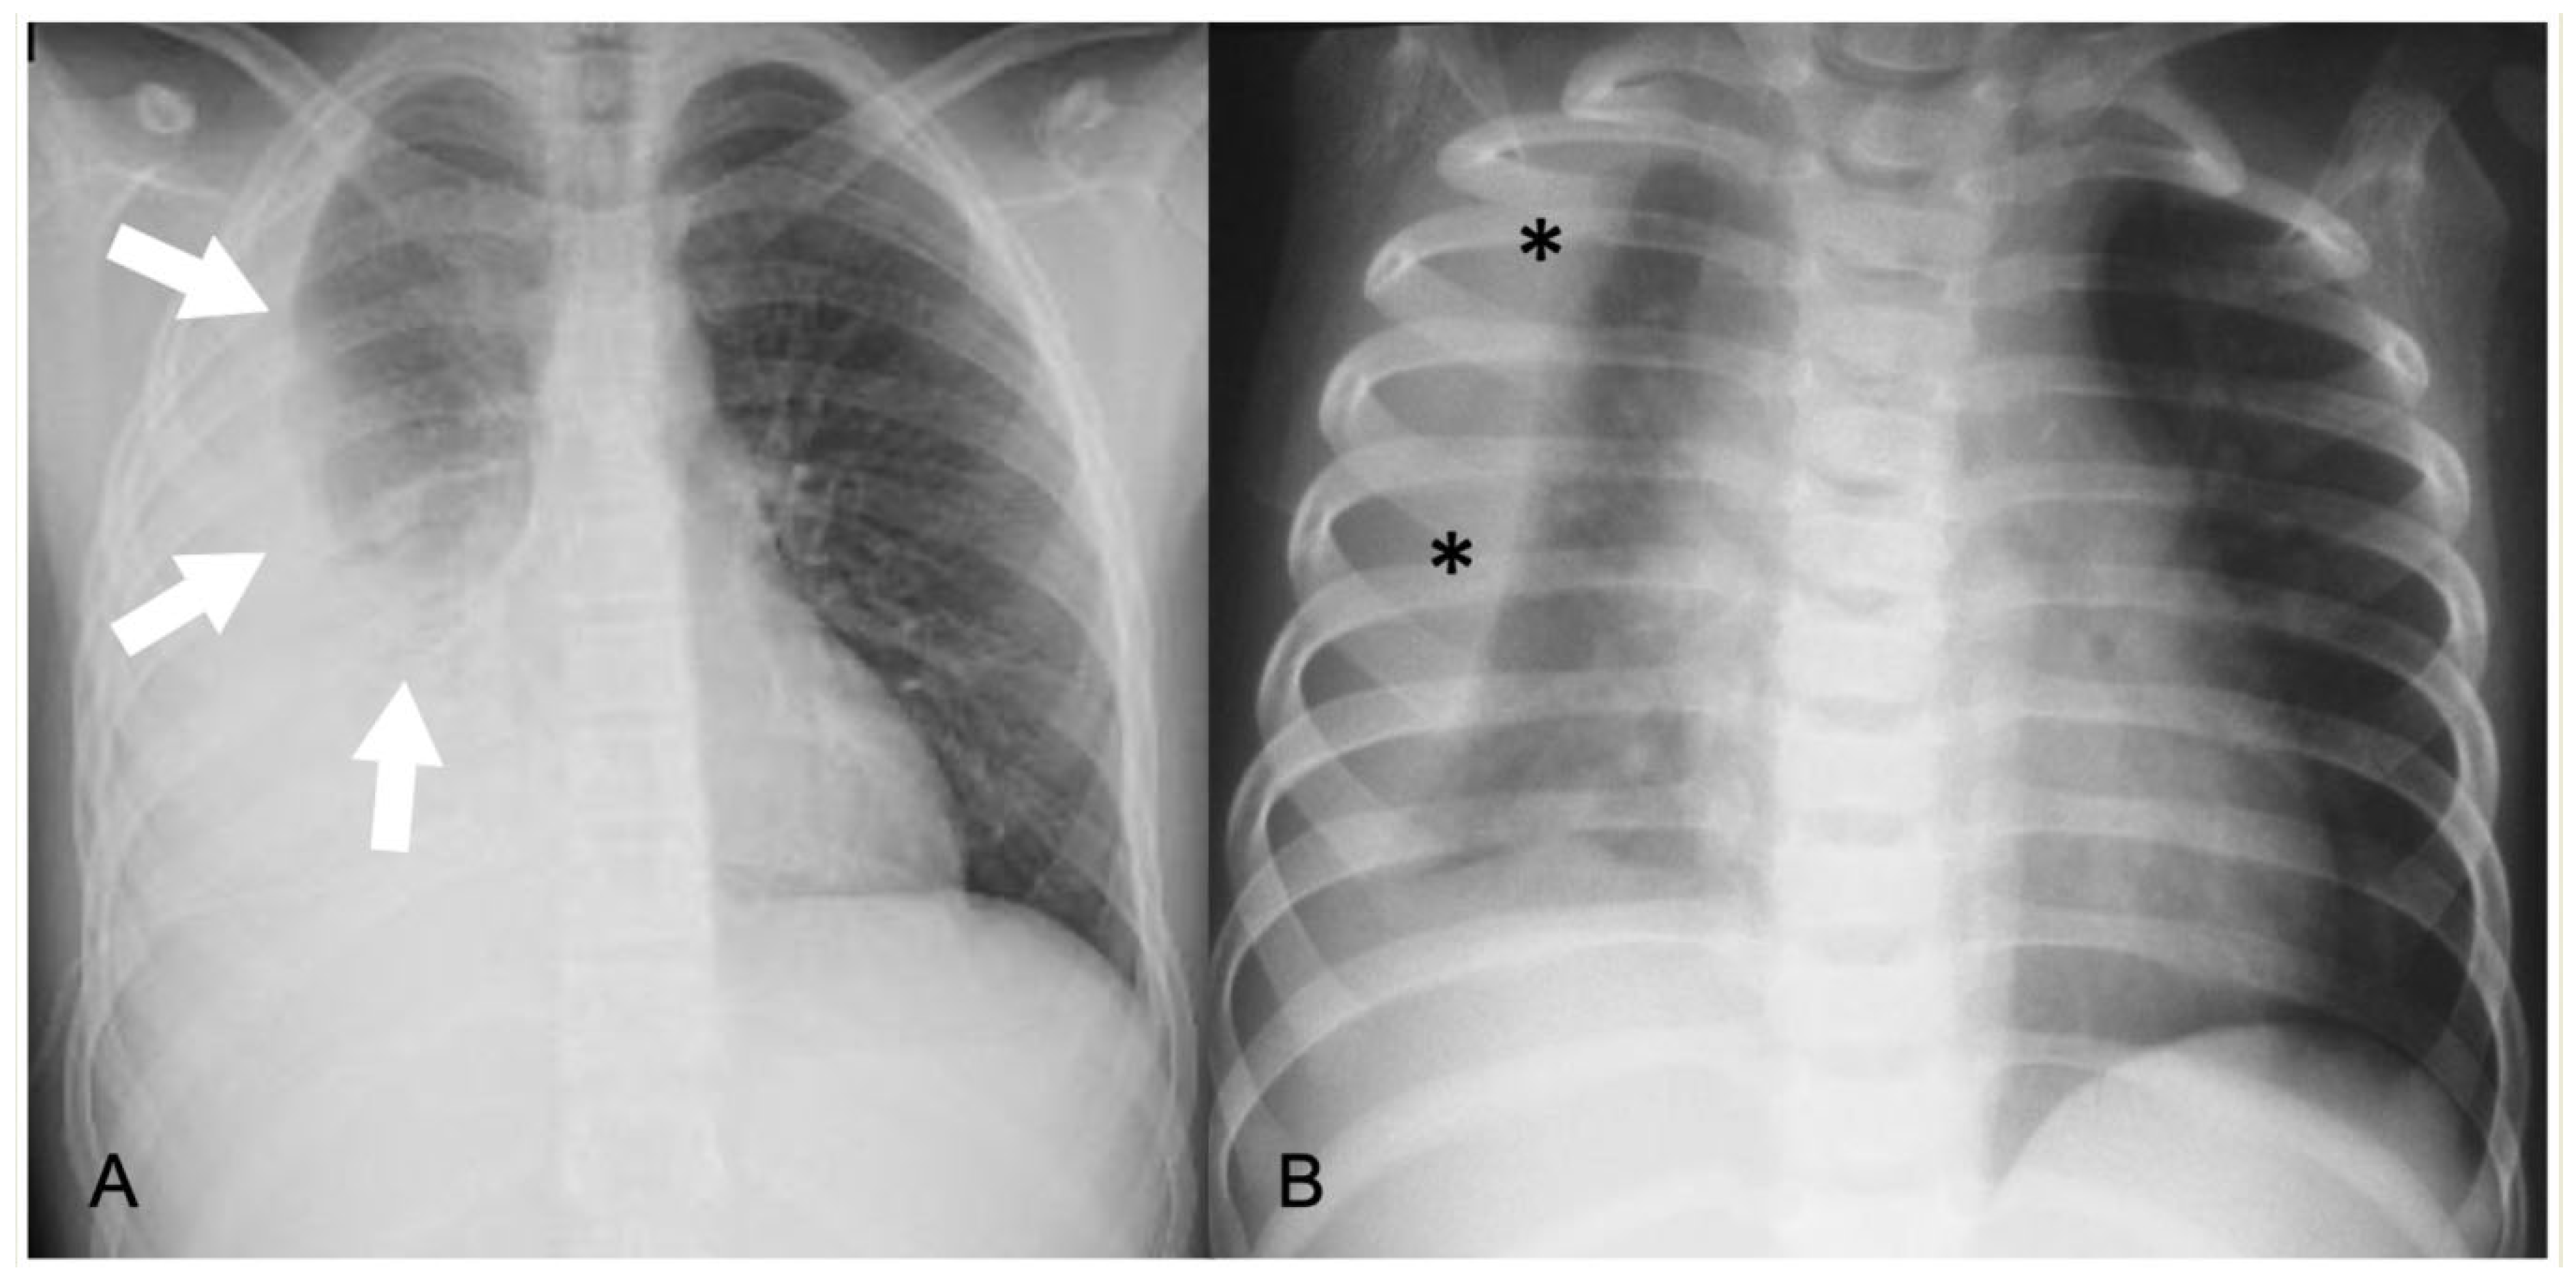

2.4.1. Pleural Effusion—Empyema